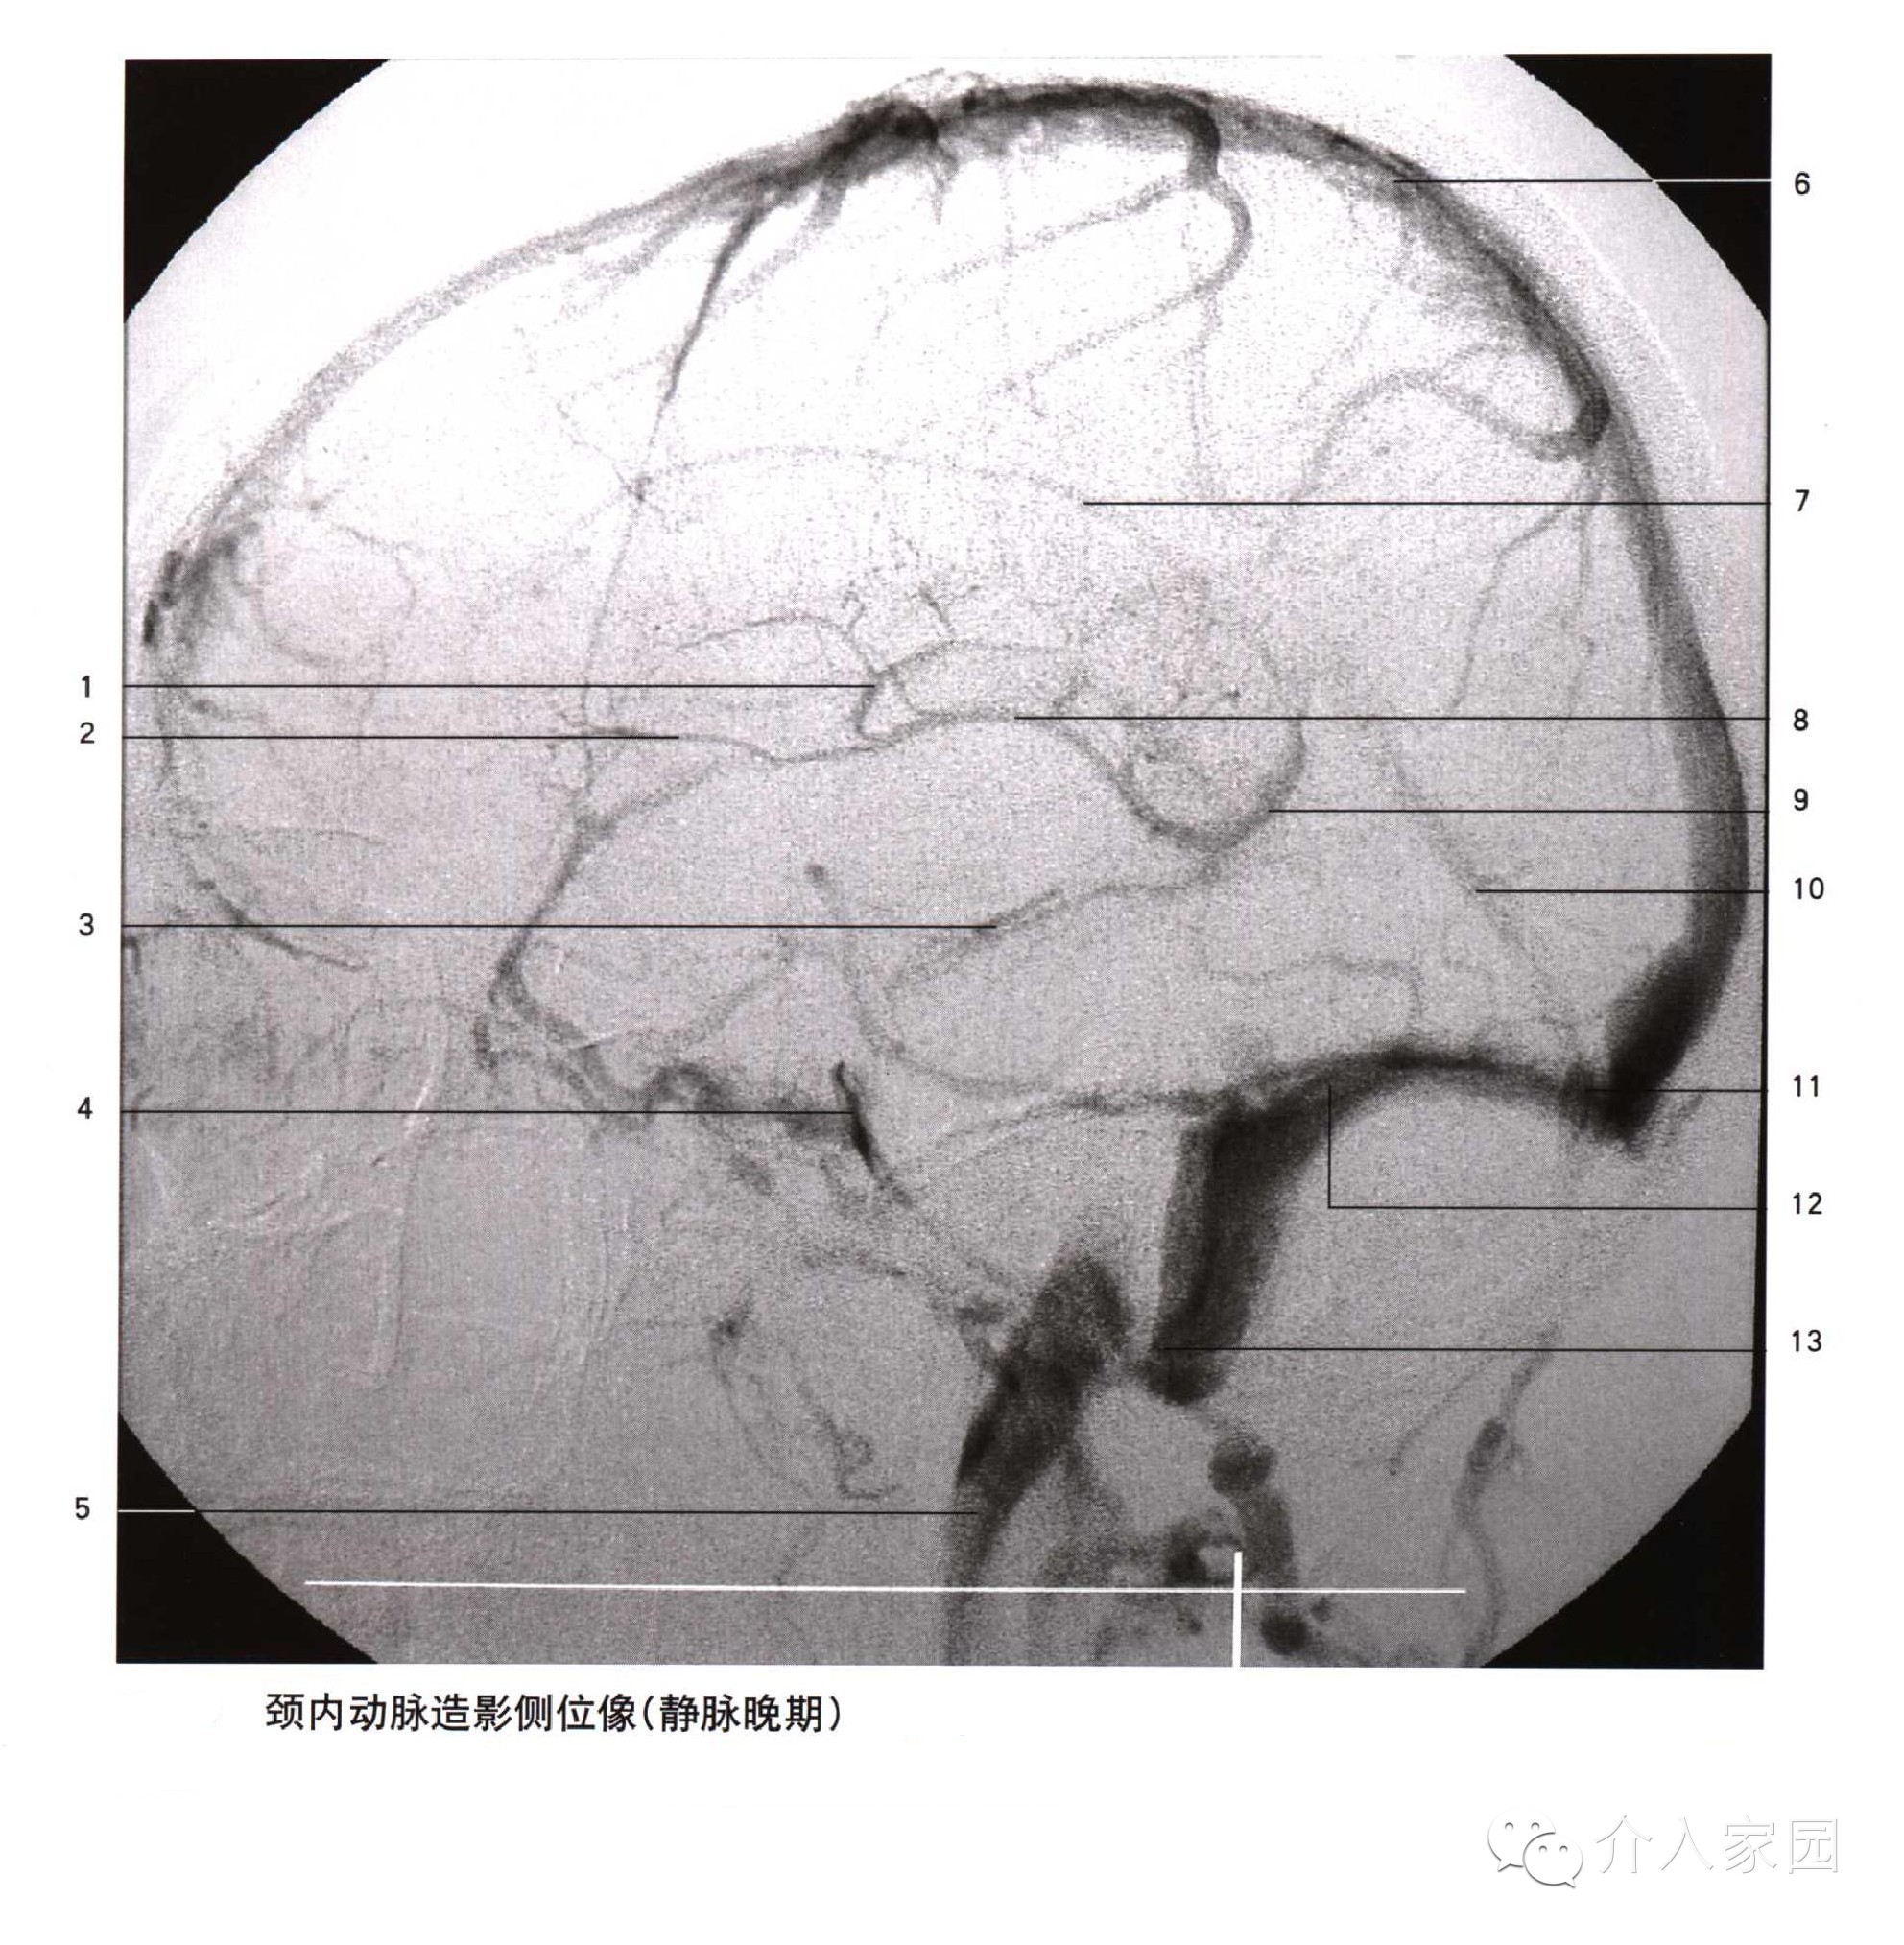

1、上吻合靜脈 2、額升靜脈 3、大腦中淺靜脈 4、海綿竇 5、岩上竇

6、岩下竇 7、中央溝靜脈 8、頂枕升靜脈 9、顳後靜脈 10、下吻合靜脈